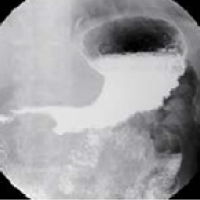

기초검사와 일반검사에서 얻은 자료를 토대로 각종 영상판독 소견을 종합하여 종합검진결과를 완성합니다. 검진결과를 참고하여 필요한 경우에는 개인맞춤 처방을 제공합니다. 또한 내과외래 진료도 진행하여 환자들의 내과진료를 담당합니다. 소화기 내과에서는 위/대장 내시경 검사 및 판독결과 상담을 통해 소화기질환 및 암검진에 대한 상담 및 처방을 진행합니다.